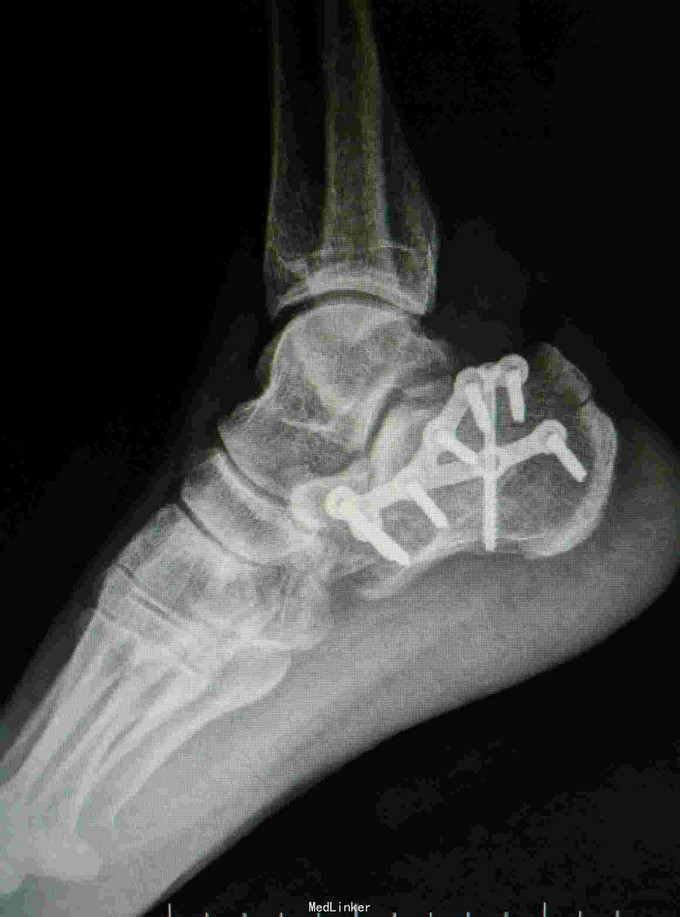

诊断:右跟骨粉碎性骨折 治疗:骨折切开复位内固定

随访:3月内避免患肢负重,3月后视复查情况决定是否负重,行功能锻炼。 讨论:跟骨骨折有部分患者远期效果并不特别好,尤其是骨折涉及关节面,术中应尽量复位。还有就是需要视软组织情况选择合适的固定方式。